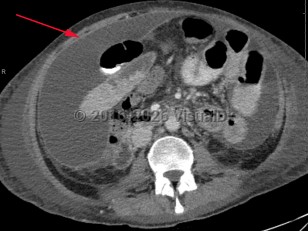

Imaging Studies image of Peritonitis - imageId=8341512. Click to open in gallery.  caption: '<span>Enhanced axial CT scan of the abdomen and pelvis demonstrates large amount of loculated peritoneal fluid with enhancing rim in the abdomen and pelvis.</span>'

Enhanced axial CT scan of the abdomen and pelvis demonstrates large amount of loculated peritoneal fluid with enhancing rim in the abdomen and pelvis.